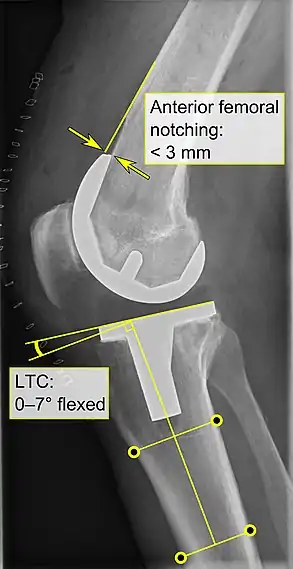

Knee replacement is routinely evaluated by X-ray, including the following measures:

- FTC: frontal tibial component angle, which is regarded as optimal when being at a right angle. A varus position of more than 3° has generally been found to increase the failure rate of the prosthesis.[57] - Anterior femoral notching (the femoral component causing reduced thickness of the distal femur anteriorly), seems to cause an increased risk of fractures when exceeding about 3 mm.[58]

- Anterior femoral notching (the femoral component causing reduced thickness of the distal femur anteriorly), seems to cause an increased risk of fractures when exceeding about 3 mm.[58]

- LTC: lateral (or sagittal) tibial component angle, which is ideally positioned so that the tibia is 0–7° flexed compared to at a right angle with the tibial plate.[57]